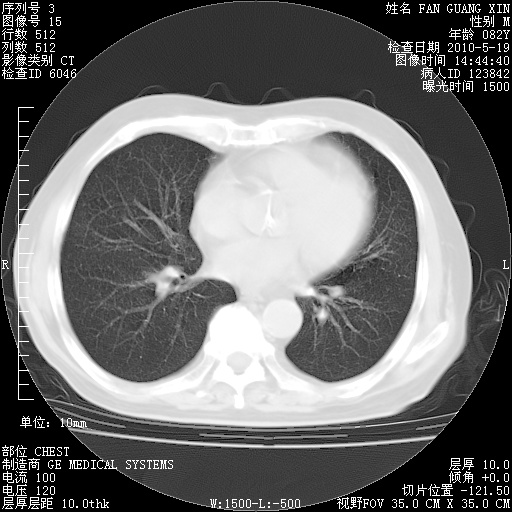

复查肺部CT,明显好转。为什么发热呢?

治疗3周后的肺部CT